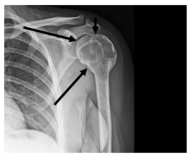

A imagem apresenta uma radiografia do ombro esquerdo do paciente.

A região assinalada na imagem é denominada: